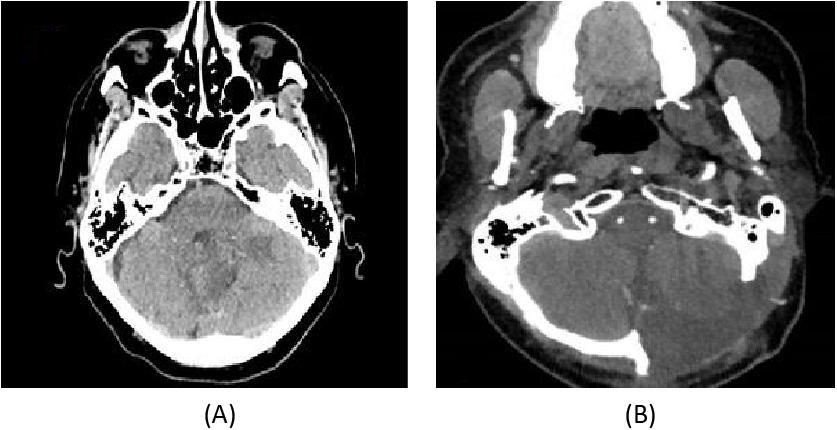

The patient underwent macroscopically complete surgical excision after craniectomy of the posterior fossa (Fig. 2B) compared with preoperative brain scan sections (Fig. 2A), and the anatomopathological examination concluded that it was an IDH1 non-mutated glioblastoma, p53 positive, ATRX positive, MGMT-positive with 1P19Q codeletion (Fig. 3).

Fig. 2. (A) CT scan axial preoperative brain scan sections. (B) CT scan axial control after craniectomy of the posterior fossa.